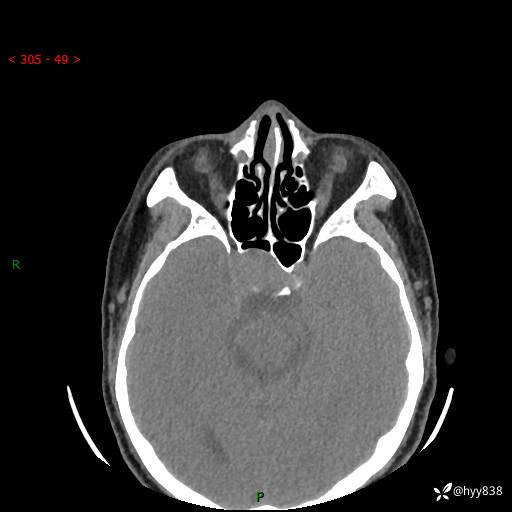

蝶鞍CT平扫